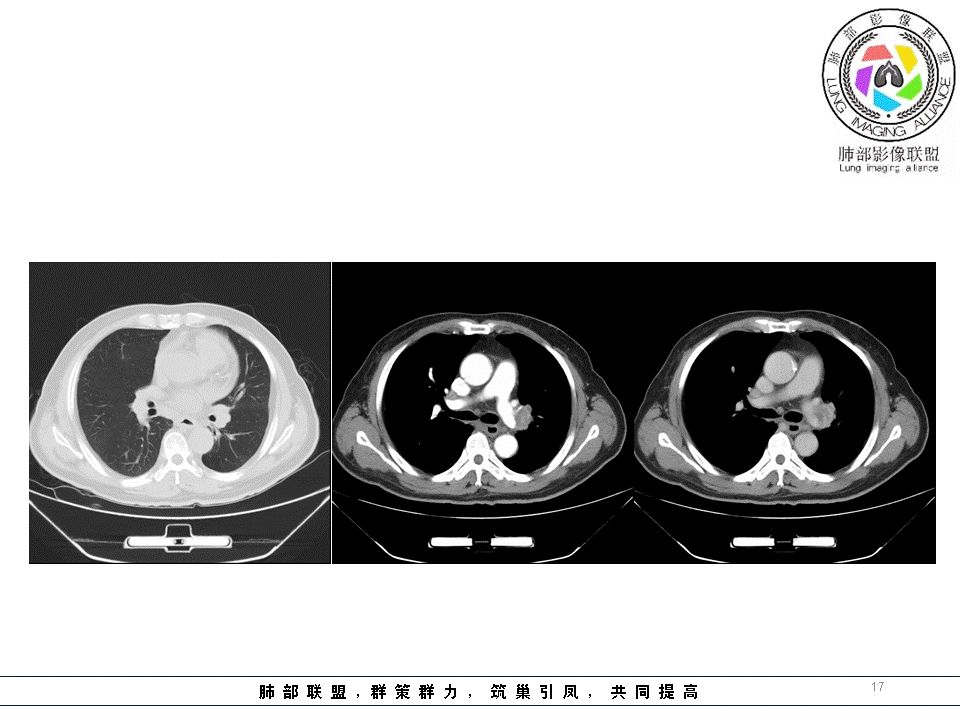

小溪流:中纵隔、左肺门多发肿物,均匀强化,气管、支气管受压,考虑淋巴瘤可能

平安是福:纵隔及肺内多发淋巴结肿大,部分融合,部分淋巴结内可见坏死,环形强化,考虑淋巴结结核,鉴别淋巴结转移。

淋巴瘤不治疗坏死不常见

左伯强巨野县北城医院:

结核。淋巴结坏死,周边强化曹志勇:纵隔及左肺门占位,周围组织受压移位,气管似有变窄明显不均匀强化,考虑恶性,淋巴瘤来源可能大云荼:纵膈及左肺门区肿物,呈环形强化,其内有坏死,左侧气管支气管受侵变窄。考虑恶性,淋巴瘤可能性大,不除外结节病?

春秋:左肺门及纵隔多发肿大淋巴结,强化示不规则坏死,坏死边界不清,左主支气管管壁不规整!整体考虑恶性病变,转移可能性大!

小微:纵隔多发淋巴结淋巴结肿大,增强扫描无明显强化。左肺门淋巴结肿大,颈部及锁骨上区淋巴结肿大,考虑淋巴瘤。鉴别诊断转移瘤。

心灵鸡汤:左肺上叶条状斑片影,纵隔2 3 4 5 6 7 10 11组多发淋巴结肿大,增强后中央坏死区不强化,边缘见强化,邻近气管受压变窄,偏向恶性,左上肺腺癌并淋巴结转移可能,淋巴瘤?巨淋巴细胞增生?继发性结核?请各位老师指点

小景:左肺舌段支气管狭窄,纵隔及左肺门多发肿大淋巴结,部分坏死环形强化。考虑肺癌淋巴结转移。鉴别支气管内膜结核。

王秀仙:纵隔及肺门多发淋巴结肿大,部分淋巴结内可见坏死,环形强化,气管受压变形,左肺门淋巴结较大,压迫上叶支气管开口,左上肺可见条索,考虑淋巴结转移。鉴别结核。